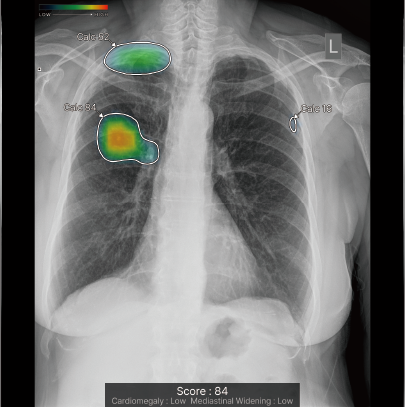

CXR-AIDが候補領域の解析をおこなったのち、0~100に応じた確信度を色分けして表示。

検出領域ごとに所見名を表示します。

対象所見のそれぞれの確信度の最大値が所見ごとに個別に表示されます。

ヒートマップと輪郭の表示は3パターンから選択可能です。